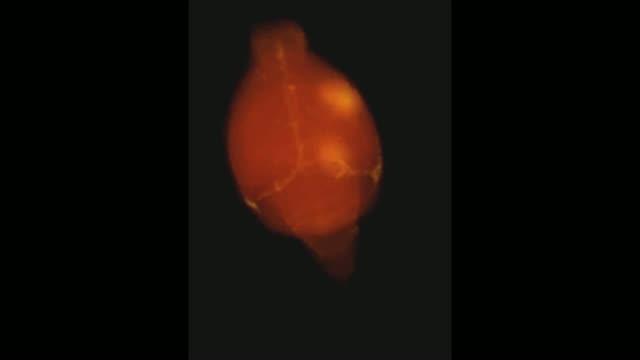

video: Focused ultrasound-induced blood-brain barrier openings in a mouse brain.

Maria Eleni Karakatsani/Columbia Engineering